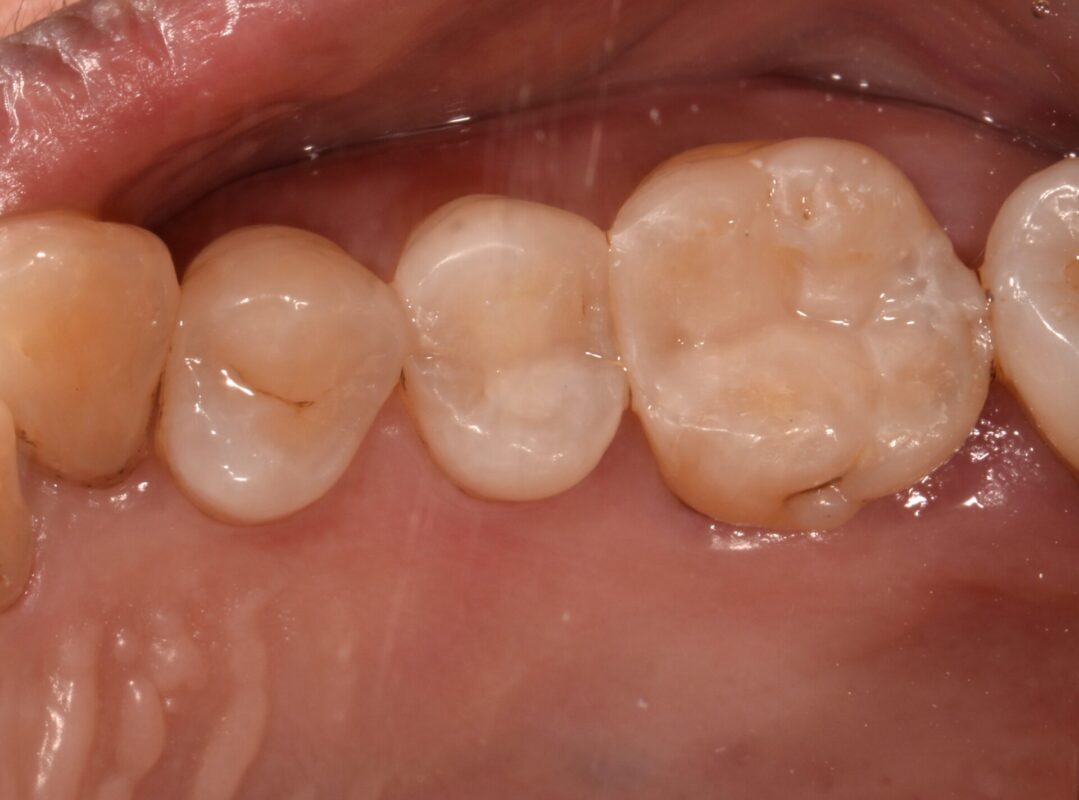

歯根破折歯の治療

コンポジットレジン充填後

内部にも充填して可能な限り接着しています。

術後2年経過していますが、今のところ問題ないです。